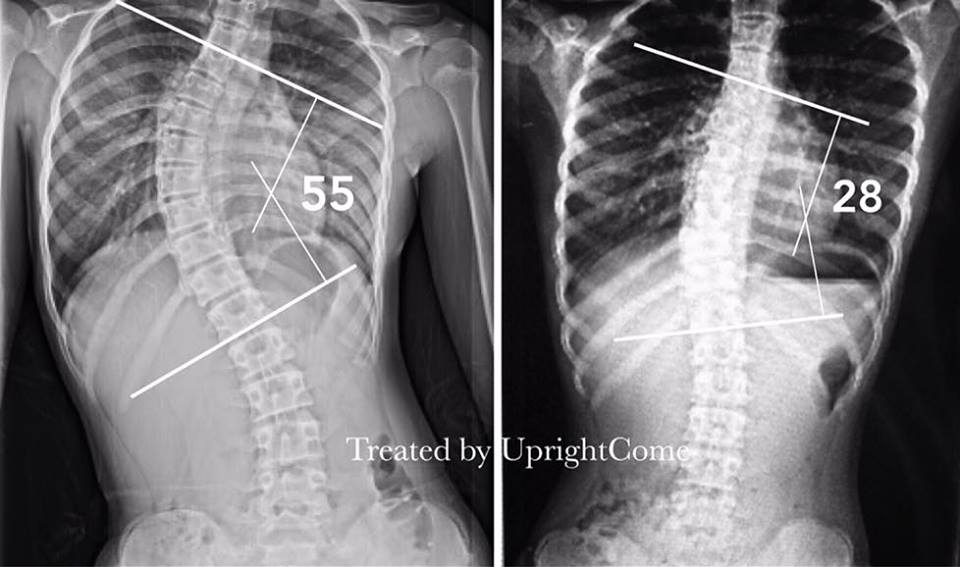

A 12-year-old girl with severe scoliosis in 55 degrees from Taipei

The X-ray after three-month treatment brought relief to the parents of the patients.